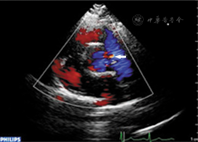

对于本例患者,术前超声未发现瘘口,仅表现为左心增大。造影发现冠状动脉瘘后,回放患者超声图像,大动脉根部短轴观可见自左冠状动脉至肺动脉的异常分流及自右冠状动脉至肺动脉的异常分流(图2)。

冠状动脉瘘为先天或后天冠状动脉畸形的一种[1]。瘘口大小及引流部位不同,可引起不同的血液动力学影响,对于分流严重、症状明显的患者,及时治疗十分必要[2]。目前冠状动脉造影仍为诊断冠状动脉瘘的金标准,但超声心动图、磁共振、CT等影像学方法均为重要的无创检查手段[3]。特别是综合超声心动图检查技术可作为冠状动脉瘘的首选检查方法。超声心动图诊断冠状动脉瘘受瘘口大小、瘘管粗细及引流部位的影响[2]。本例中多个瘘口引流至肺动脉者实属罕见,常规超声心动图切面难以显示完整的血管走行,需采用多声窗、多切面调整探头角度进行追踪。应注意冠状动脉起始部位有无增粗,冠状动脉内径有无扩张。冠状动脉瘘开口于肺动脉,类似于动脉导管未闭时连续性左向右分流,引起左心容量负荷过重[4],可出现左心增大及肺高压征象。在二维超声引导下,通过彩色多普勒可测及瘘口处五彩镶嵌的异常分流信号[1]。因肺动脉压力较主动脉压力低,故瘘口处应为连续性分流信号。同时,若冠状动脉瘘造成主动脉或心腔扩大,可有相应的瓣膜反流信号。频谱多普勒技术于瘘口处可测及连续的湍流信号,同时因左室舒张末压增高,肺静脉血流频谱可见钝圆的小S波[5]。由于左向右分流造成肺血流量增加,可形成肺高压,根据跨三尖瓣收缩期反流压差或肺动脉瓣血流加速时间测得的肺动脉压力会相应增高。